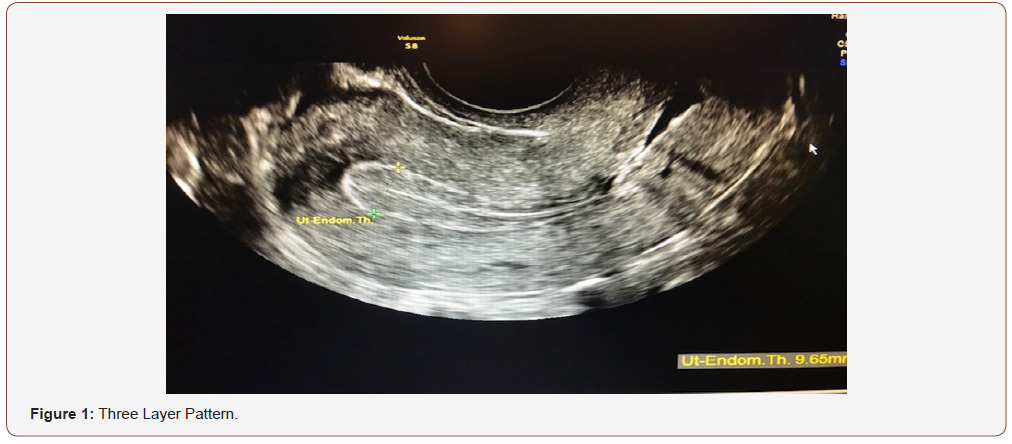

An evaluation of endometrial morphology included an assessment of endometrial echogenicity, the endometrial midline and the endometrial-myometrial junction. A ‘uniform’ endometrium included the three-layer pattern (Figure 1), as well as a homogenous hyperechogenic, hypoechogenic and is echogenic endometrium. The echogenicity is defined as ‘non-uniform’ if the endometrium appears heterogenous, asymmetrical or cystic (Figure 2). The endometrial midline was defined as ‘linear’ (Figure 3), if a straight hyperechogenic interface within the endometrium is visualized, as ‘non-linear’ if a waved hyperechogenic interface is seen, and as ‘irregular’ or as ‘not defined’ in the absence of a distinct interface (Figure 4). All studies were performed at the AIUM certified sonographic unit.